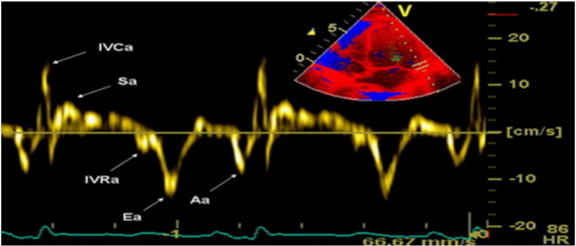

Tissue doppler imaging-TDI

Tissue Doppler Imaging is more sensitive diagnostic method than Pulsed-wave Doppler analysis. It is relatively load independent and better reflects LV function in patients with heart failure with preserved ejection fraction. The technique is based on the following principle: in the apical, 4-chamber position, a 2-5mm sample volume is placed of the mitral ring, medial (septal) and lateral segment, to measure velocity of longitudinal motion (shortening and lengthening). Mitral annulus moves toward the top of the LV, in systole, and away from the top in the diastole phase. S-(systolic) wave, E’ and A’-wave (diastolic waves) are recorded. E’-wave (early diastolic velocity) reflects LV relaxation (elongation) while A’-wave (late diastolic velocity) reflects LA contraction and late LV filling (shortening). E’-wave progressively decreases with decreasing of longitudinal lengthening (relaxation) in various pathological conditions. It is one of the earliest markers of diastolic dysfunction and is present in all stages. Recent data suggest that the velocity at the septal corner can be influenced by various factors (LV filling) and can be reduced in patients with normal LV function. Therefore, it is preferred to measure the velocity of the lateral segment of the mitral annulus (Figure 5).12 The E’ wave at the lateral segment, greater than 10 is considered normal, while E’ less than 10 is indicator of increased LV filling pressure. The E’ wave at the septal segment, greater than 8 is considered normal, while E’ less than 8 is indicator of increased LV filling pressure. Nagueh et al.10 noted that E/E’ ratio gives more accurate estimation of LV filling pressure than E-wave velocity. The E/E’<8 is considered normal LV filling pressure. Value ​​greater than 15 is indicative of increased, while the value ​​from 8 to 15 is considered as slightly increased LV filling pressure.9,13 Table 1 represent the normal velocities of septal and lateral E’-waves, depending on age. TDI has ability to distinguish normal from pseudonormal Doppler profile. Thus, Boyer et al.14 in their echocardiographic study of diabetic patients without hypertension, coronary and valve pathology, found mild diastolic dysfunction in 74% with TDI, compared to PW Doppler analysis with Valsalva maneuver.

Figure 5 TDI of the lateral segment of the mitral annulus.12